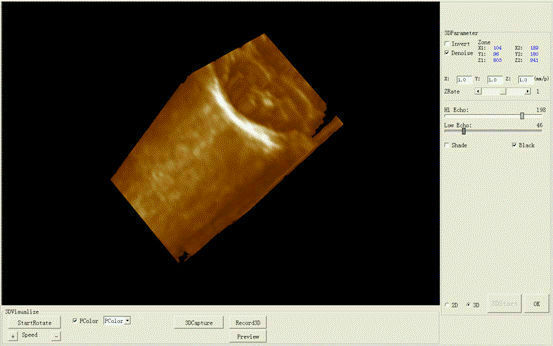

Designed with portability and functionality in mind, the New Portable Notebook Digital Laptop Machine offers superior performance without compromising on ease of use. Its compact size allows for easy transport and setup, while the digital laptop interface ensures that users can quickly access and utilize the scanner's capabilities. The inclusion of a convex probe and 3D imaging further enhances the diagnostic accuracy, providing clearer and more detailed images than ever before.

In addition to its user-friendly design, the New Portable Notebook Digital Laptop Machine provides high-resolution imaging that is crucial for accurate diagnostics. The 3D imaging capability allows for more comprehensive assessments of anatomical structures, leading to better treatment planning and patient management. Whether used for routine check-ups or complex medical evaluations, this ultrasound scanner delivers reliable and precise results.